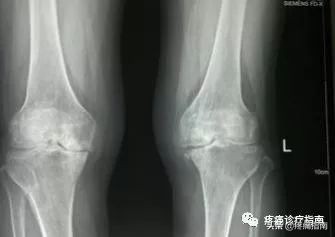

8.影像检查

X线摄片为骨性关节炎的常规检查,早期多正常,中晚期可见关节间隙不对称狭窄,关节面下骨硬化和变形,关节边缘骨赘形成及关节面下囊肿和关节腔游离体。根据Kellgren和Lawrecne的放射学诊断标准,骨性关节炎分为5级。0级正常。I级关节间隙可疑变窄,可能有骨赘。II级有明显的骨赘,关节间隙轻度变窄。III级中等量骨赘,关节间隙变窄较明确,软骨下骨质轻度硬化改变,范围较小。IV级大量骨赘形成,可波及软骨面,关节间隙明显变窄,硬化改变极为明显,关节肥大及明显畸形。

①膝关节骨关节炎临床诊断标准:近1个月内大多数时间有膝关节疼痛;膝关节活动时有摩擦音;晨僵<30min;年龄≥38岁;膝关节检查有骨性肥大。满足①+②+③+④条,或①+②+⑤条或①+④+⑤条者,可诊断为膝关节骨关节炎。

②膝关节骨关节炎临床及放射学诊断标准:近1个月内大多数时间有膝关节疼痛;X线示关节边缘骨赘;关节液实验室检查符合关节炎;晨僵<30min;年龄≥40岁;膝关节检查有骨性肥大。满足①+②条,或①+③+⑤+⑥条或①+④+⑤+⑥条者,可诊断为膝关节骨关节炎。